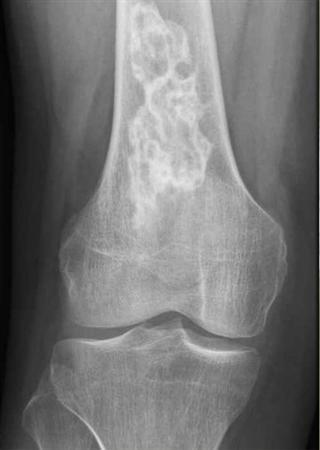

Diagnosis?

Paget’s

Note lytic, sclerotic and mixed lesions in bone, representing all 3 phases of Paget’s disease

Increased bone turnover due to increased osteoclastic bone resorption and abnormal bone remodeling